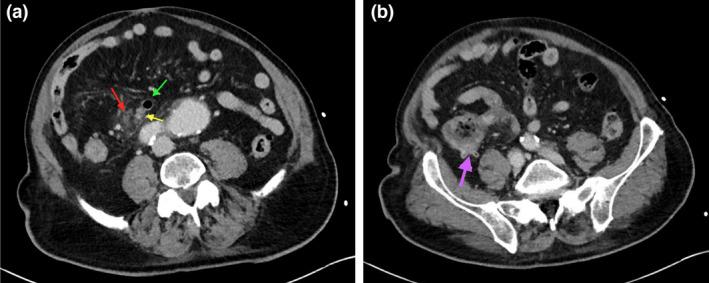

Complicated appendicular diverticulitis.

Appendiceal diverticulitis, a frequently underdiagnosed entity, differs from typical appendicitis by the presence of an inflamed appendiceal diverticulum. Appendiceal diverticulitis is a surgical emergency which has an increased risk of perforation compared to typical appendicitis. We will discuss a surgically and pathologically confirmed case of complicated appendiceal diverticulitis and its management implications.